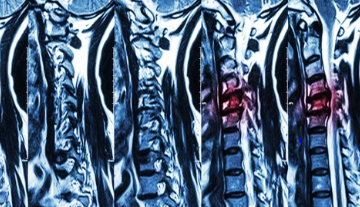

허리디스크는 많은 현대인들이 겪고 있는 흔한 질환 중 하나입니다. 이는 척추 뼈 사이에 위치한 디스크가 손상되어 신경을 압박하게 되면서 발생하는 통증과 다양한 증상을 유발합니다. 전조증상으로는 허리의 불편함과 통증이 점차적으로 시작되며, 이는 다리까지 방사되는 경우도 있습니다. 조기 발견과 적절한 치료가 중요한데, 이는 증상의 악화를 막고, 더 나은 삶의 질을 유지할 수 있게 도와줍니다. 비수술적 치료방법부터 수술적 치료까지 다양한 옵션이 있으며, 환자의 상태와 증상에 따라 최적의 치료 계획을 세울 수 있습니다. 이 글에서는 허리디스크의 전조증상을 인지하는 방법과, 효과적인 치료 방안에 대해 자세히 알아보겠습니다. 오늘은 허리 디스크 전조증상 및 치료방법에 대해 알아보겠습니다.

허리디스크는 많은 현대인들이 겪고 있는 질환 중 하나로, 척추의 디스크가 탈출하거나 손상되어 신경을 압박함으로써 발생하는 통증 및 기타 증상을 일으키는 상태를 말합니다. 이 질환은 잘못된 자세, 과도한 체중, 또는 반복적인 스트레스 등 다양한 원인에 의해 발생할 수 있으며, 특히 장시간 앉아 있는 생활습관이 있는 사람들에게서 자주 발견됩니다. 전조증상으로는 허리 통증, 다리 저림, 감각 이상 등이 있으며, 이러한 증상들은 일상생활에 큰 불편을 초래할 수 있습니다. 치료 방법은 증상의 정도와 개인의 상태에 따라 다르지만, 일반적으로는 물리치료, 약물치료, 그리고 필요한 경우 수술적 치료가 고려될 수 있습니다. 조기 진단과 적절한 치료 계획을 통해 허리디스크로 인한 통증과 불편을 줄이고, 건강한 척추 상태를 유지할 수 있습니다.

허리 디스크, 또는 추간판 탈출증은 척추의 디스크가 제자리에서 벗어나 주변 신경을 압박하는 상태를 말합니다. 이로 인해 통증, 저림, 감각 이상 등 다양한 증상이 나타날 수 있습니다. 허리 디스크의 가장 흔한 증상은 허리 통증이며, 이 통증은 다리로 방사될 수도 있습니다. 또한, 디스크가 신경을 압박하면 해당 신경이 지배하는 영역에 감각 이상이나 근력 약화가 발생할 수 있습니다.